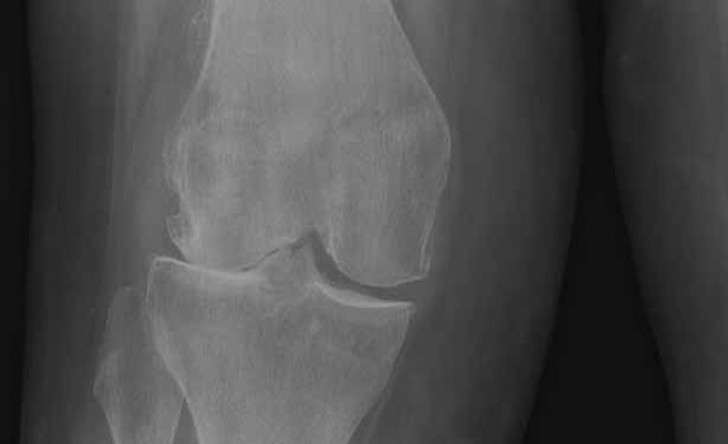

Our services are lead by Simon Palmer who is a Consultant Orthopaedic Surgeon with specialist training and experience in all aspects of knee surgery, including minimally invasive surgery and partial knee replacement.